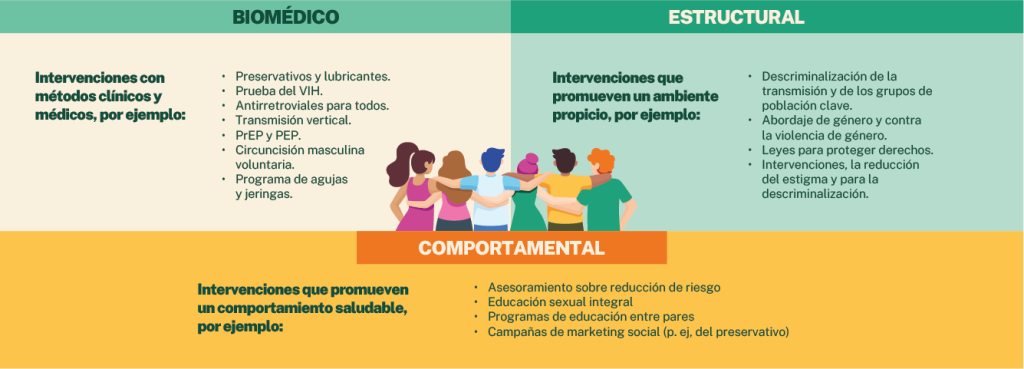

¿Sabes qué es la prevención combinada?

El Programa Conjunto de las Naciones Unidas sobre el VIH/Sida (ONUSIDA) la define como el conjunto de programas comunitarios fundamentados en los derechos y la evidencia. Promueve una combinación de intervenciones biomédicas, comportamentales y estructurales, diseñadas para satisfacer las necesidades de prevención de la infección por el VIH en personas y comunidades específicas. Busca disminuir el número de nuevas infecciones con actividades de impacto sostenido de mayor magnitud (Prevención Combinada de la Infección por el VIH, s.f.).

¿Conoces los enfoques de la prevención combinada?

- Basada en la evidencia

La acción preventiva en la respuesta al VIH considera los avances de la ciencia, los estudios y los aportes cualitativos y cuantitativos, con los que contribuyen los diferentes programas para la prevención del VIH desde los enfoques biomédicos, comportamentales y estructurales. Esto puede permitirte más rigurosidad técnica y científica en la oferta de servicios y paquetes combinados.

- ¿Cómo se da la intervención biomédica?

- Conoce la intervención que promueve un ambiente propicio – Garantía y reivindicación de los derechos humanos – (Estructurales)

- Conoce la intervención que promueve un comportamiento saludable (COMPORTAMENTAL)

Para disminuir el riesgo de contraer alguna ITS o el VIH, debes comprender el riesgo al que te expones y contar con los conocimientos, las aptitudes y la confianza en tu propia capacidad para reducirlo. Las intervenciones sobre el comportamiento basadas en la evidencia dan la información, la motivación y la educación, y fomentan las capacidades que ayudan a las personas a disminuir comportamientos peligrosos y mantener este cambio positivo.

Las intervenciones de modificación del comportamiento basadas en la evidencia se pueden ejecutar como parte del enfoque integral de prevención combinada de la infección por el VIH.

Entre las intervenciones que plantea ONUSIDA, puedes encontrar las siguientes (Prevención Combinada de la Infección por el VIH, s.f.):

- Asesoramiento sobre reducción de riesgo.

- Educación sexual integral.

- Programas de educación entre pares.

- Campañas de marketing social (por ejemplo, sobre el uso del preservativo).